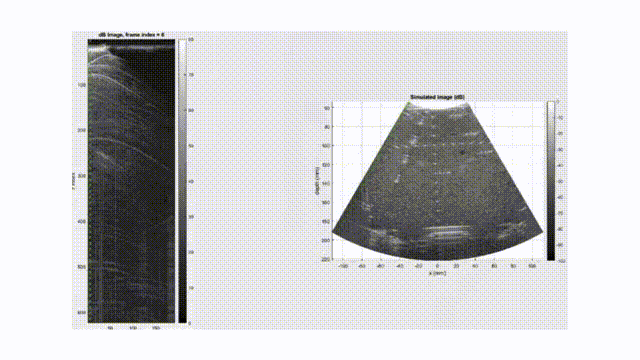

Lead research on contrast-enhanced ultrasound (CEUS) and super-resolution imaging with nanobubbles, focusing on vascular and extravascular imaging in mice.

2. Y. Weng, L. Coulter, M. S. Khan, E. Hysi, A. A. Exner, and M. C. Kolios, "Cross Amplitude Modulation and Compound Amplitude Modulation for Nonlinear Contrast-Enhanced Ultrasound Imaging of Nanobubbles," in IEEE Open Journal of Ultrasonics, Ferroelectrics, and Frequency Control, vol. 5, pp. 146-160, 2025, doi: 10.1109/OJUFFC.2025.3603792.